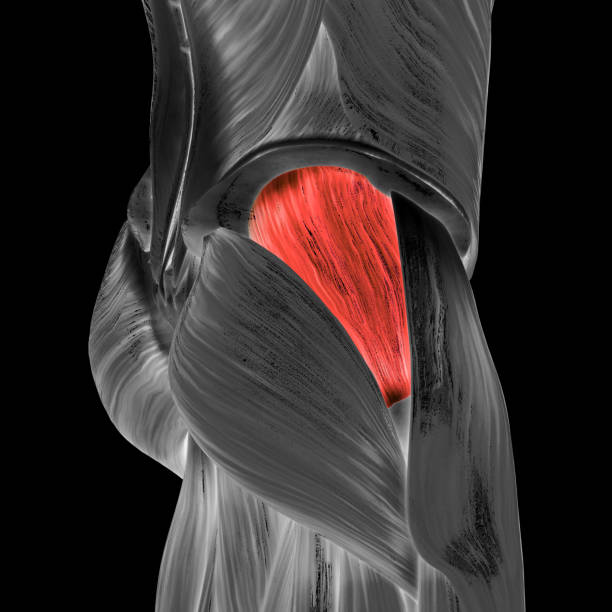

Анатомия мышц: Пириформис